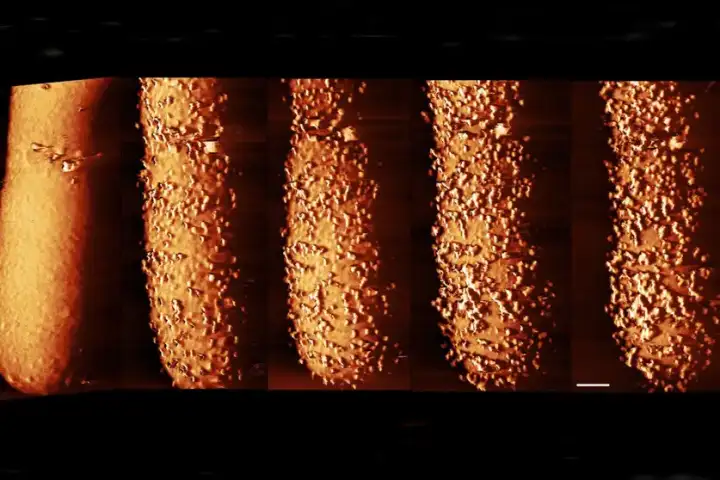

От антибиотика на бактерии вырастают странные наросты, а затем она разрушается. От антибиотика на бактерии вырастают странные наросты, а затем она разрушается.© Carolina Borrelli, Edward Douglas et al. / Nature Microbiology

При помощи атомно-силовой микроскопии, где игла толщиной всего несколько нанометров создаёт снимки, специалисты обнаружили, что полимиксин B вызывает появление странных наростов на поверхности бактерии E. coli. Через несколько минут после появления выступов бактерия начинает быстро сбрасывать липополисахариды, оставляя бреши в своей защите, которые позволяют антибиотику проникнуть внутрь и уничтожить её.